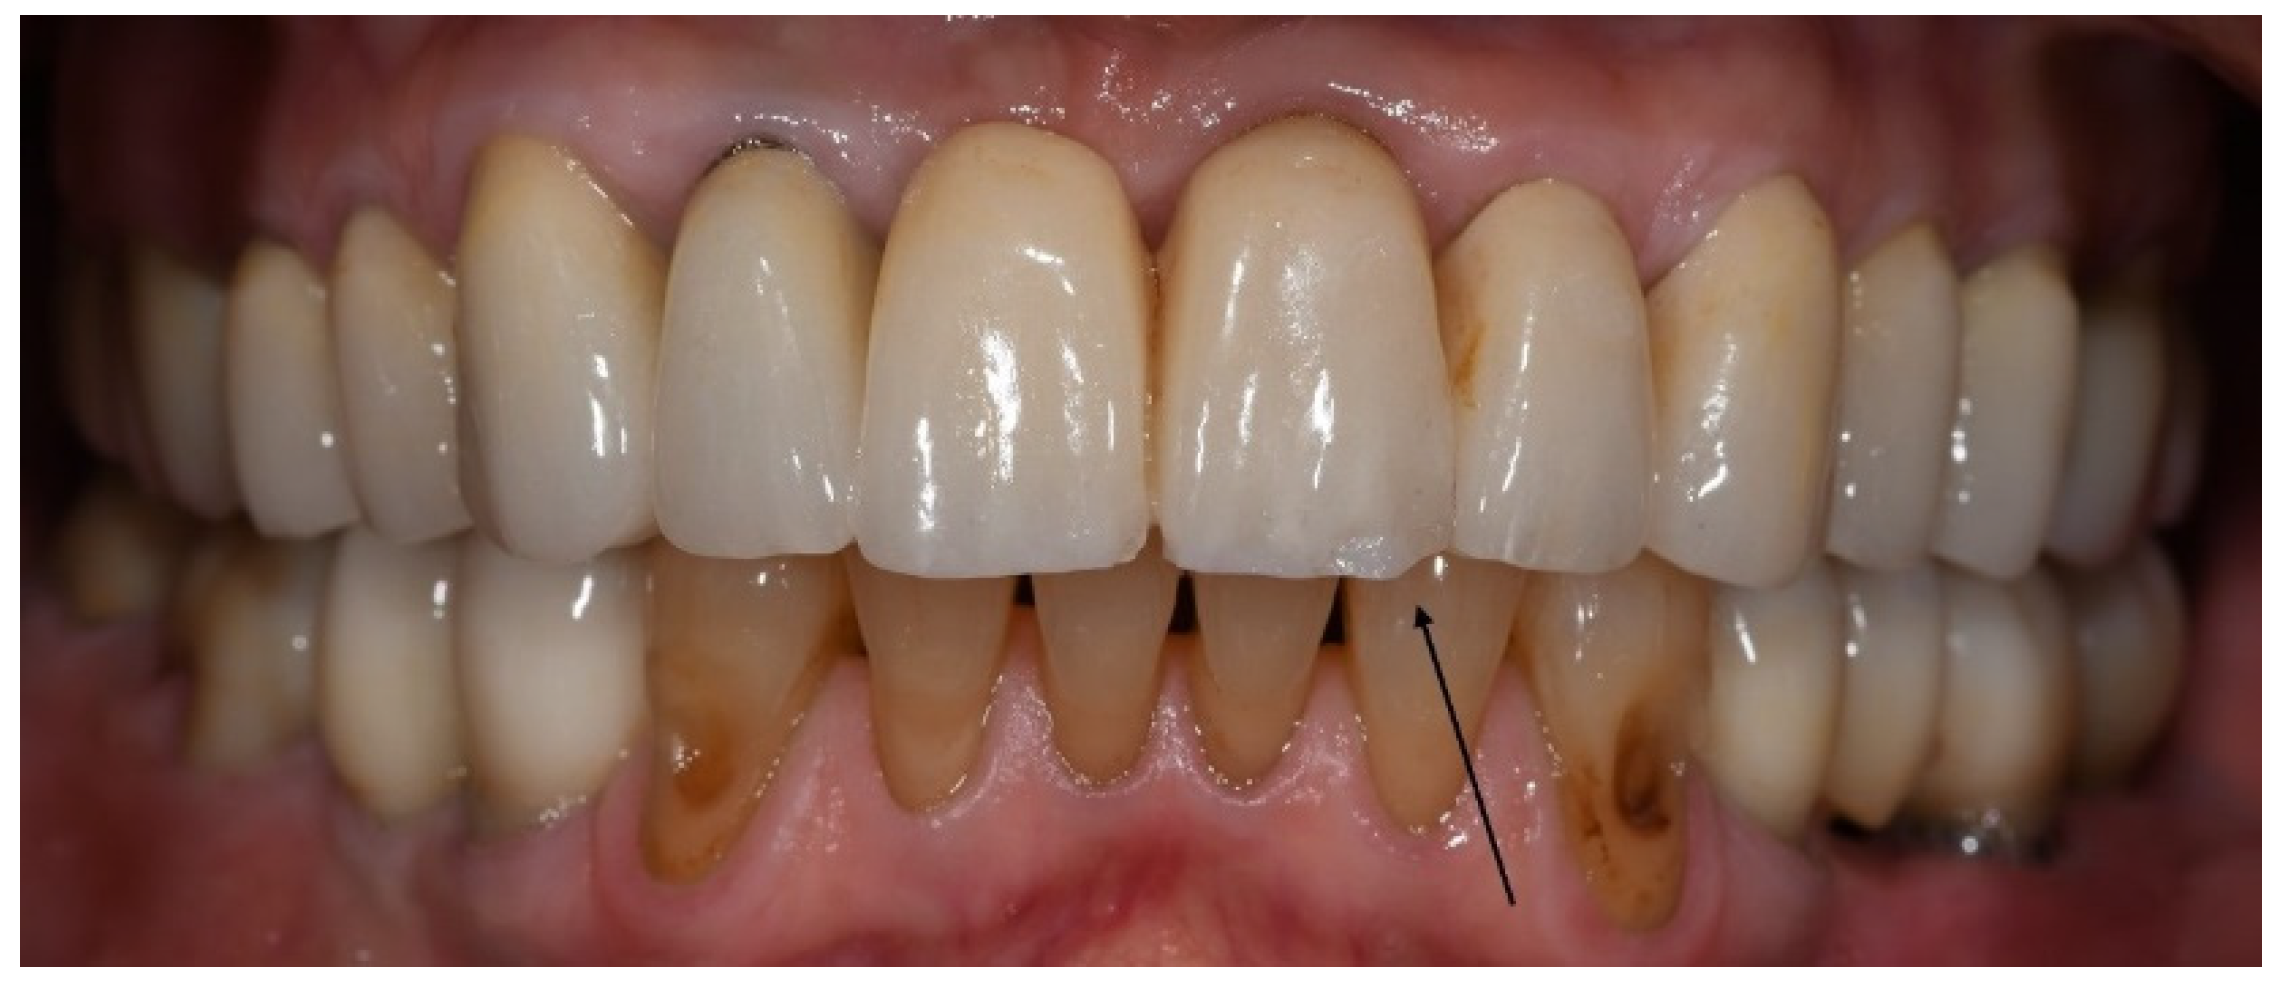

With regard to technical complications, the rate of porcelain chipping on the incisal edge of the veneered monolithic restorations was significantly higher in the bruxer group than in the non-bruxers (p = 0.045). In all cases, porcelain chipping required only polishing (grade 1); therefore, the restorations were not replaced (Figure 2).

Figure 2. Porcelain chipping on the incisal edge of the veneered monolithic restoration in the upper left central incisor, three years post-cementation. Repair required only polishing.